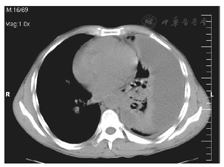

病例1尚某,男,69岁,退休干部,因晚期肝癌合并全身多发性转移,胸部CT示右侧胸腔大量积液入院,见图1。2014年12月16日入院时携带外院已行的"右侧胸腔引流管",每日控制引流胸水1 000 ml,生命征平稳,虚弱卧床,生活自理困难。入院后给予常规的支持治疗,于入院后第2日开始做胸腔三氧水灌注引流,每次注入100 ml,保留2 h后开放引流,每日2次。2 d后胸水开始明显减少,连续5 d。第5日以后24 h引流量仅有10 ml,CT检查报告为微量的积液,见图2。观察2 d无新生的胸水出现,于入院后第10日拔管,再两日患者好转出院。